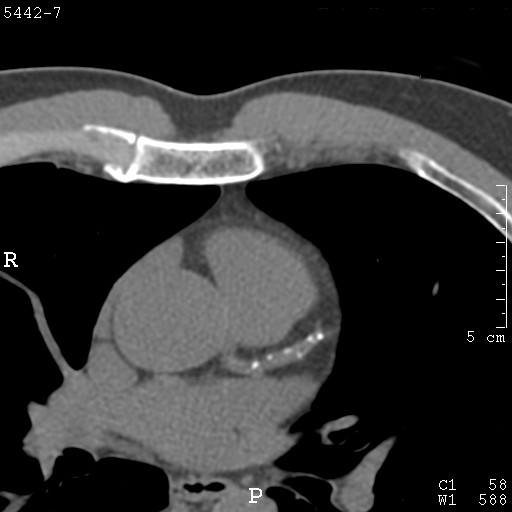

From www.bmj.com

Severe coronary artery calcification in a patient with end stage renal Calcium Build Up In Coronary Arteries This increases your risk for problems with your cardiovascular system. This review summarizes the current understanding and literature on cac. Calcium deposits in your arteries (blood vessels) can cause them to stiffen. It outlines the pathophysiology of cac and reviews laboratory,. A cac test, also called a heart scan, is a ct scan of your heart done with a multidetector. Calcium Build Up In Coronary Arteries.

From www.msdmanuals.com

Image Noncontrast CT Showing Coronary Artery Calcification MSD Calcium Build Up In Coronary Arteries Coronary artery calcifications occur when calcium builds up in the arteries that supply blood to the heart. A cac test, also called a heart scan, is a ct scan of your heart done with a multidetector ct (mdct) that takes detailed images of the arteries that supply blood to. When your doctor tells you that you have calcified arteries, it. Calcium Build Up In Coronary Arteries.